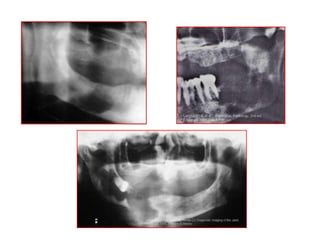

Describe? D.D?

• Solitary ill

defined

radiolucent

area related to

lower right

molars and

causing

invasion of the

IAC.

What is the view? Describe? D.D?

• Inflammatory

1. Chronic osteomyelitis

2. Osteoradionecrosis

• Neoplastic

1. Squamous cell

carcinoma

2. Metastatic tumors to

the jaws

3. Osteosarcoma and

chondrosarcoma

Multiple

punched out

areas:

Myeloma

Case study

• A 20-year old male patient

reported to the

Department of Oral

Medicine, with chief

complaint of swelling in

the lower half of the left

side of and inability to

chew food at the same

side.

• What is the D.D?